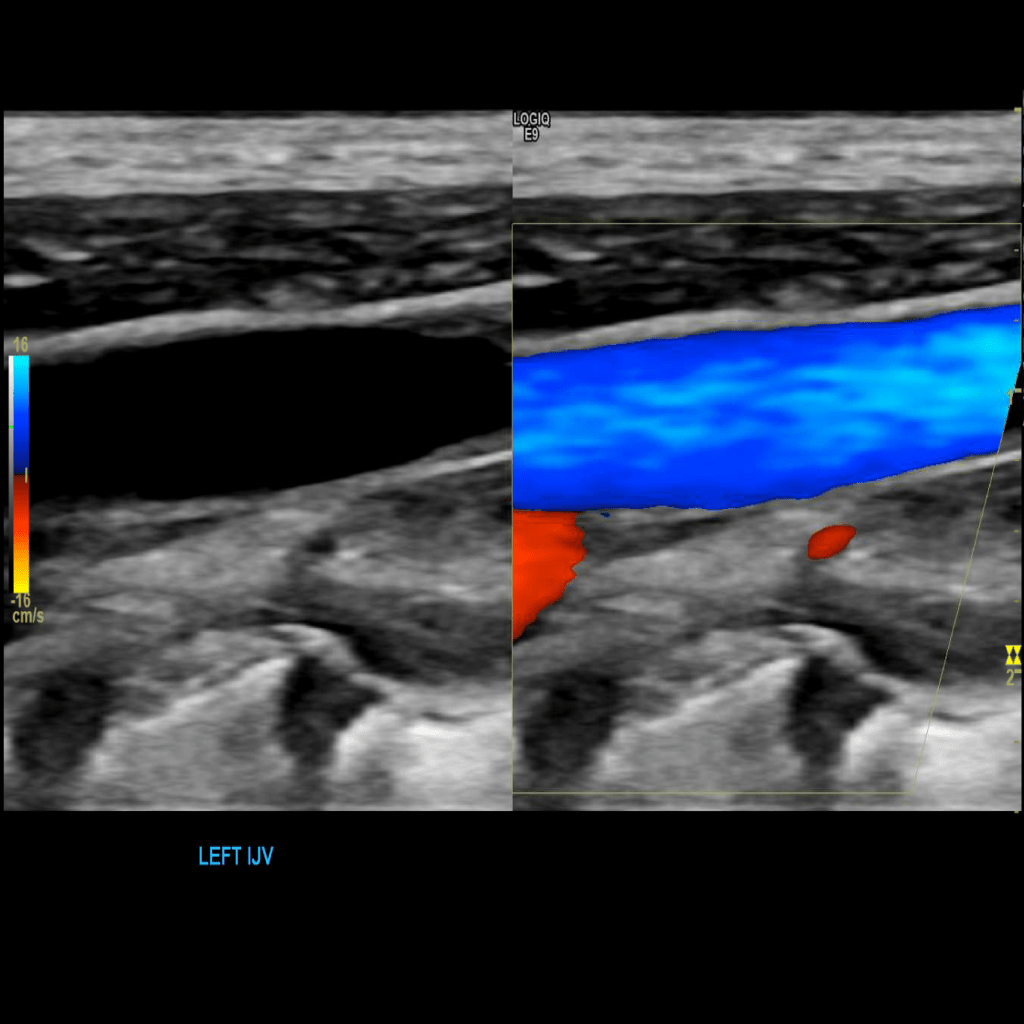

Scan the internal jugular vein in grey scale, compression, color doppler and spectral doppler